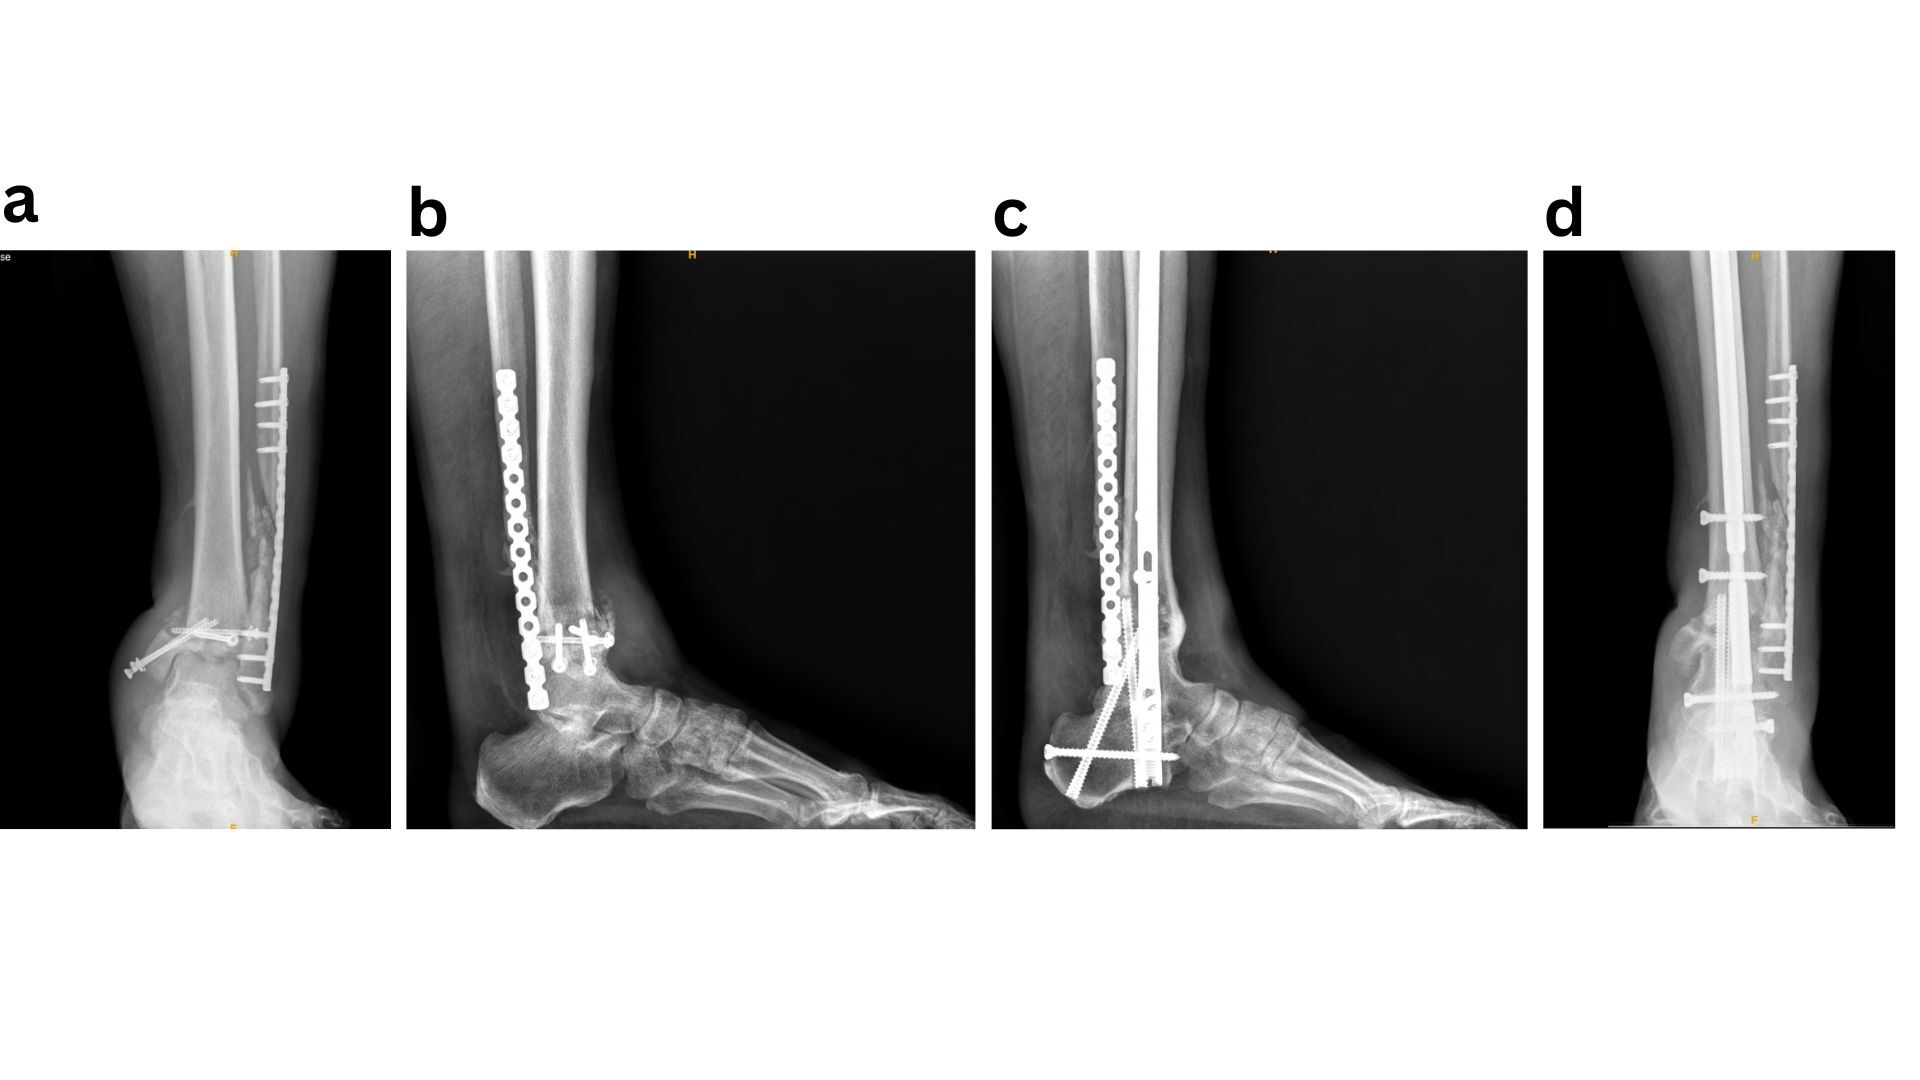

Given that the most severe complications following ORIF of diabetic ankle fractures include the development of Charcot neuroarthropathy or progression to amputation, it is logical to apply principles commonly used in Charcot reconstruction and limb salvage to this patient population. Accordingly, a “modified super construct” or “ORIF plus” strategy has been adopted for the fixation and management of diabetic ankle fractures. Sammarco et al. originally described the super construct concept in Midfoot Charcot surgery as fixation that extends beyond the zone of injury, incorporates bone resection to facilitate deformity correction and reduce soft-tissue tension, employs the strongest fixation tolerated by the soft-tissue envelope, and is applied to optimise mechanical stability.37 These principles should be adapted to diabetic ankle fractures by extending fixation beyond the immediate fracture zone, carefully planning incisions to allow fixation in areas with lower risk of wound complications, utilising the most robust fixation constructs available, and applying them in a mechanically advantageous manner, such as antiglide plating.38 The introduction of locking plate technology has significantly improved fixation in this setting by providing enhanced mechanical stability while preserving periosteal blood supply, which is critical for fracture healing, often without increasing implant bulk. In addition, the use of multiple tricortical/ quadricortical syndesmotic screws has been advocated. In neuropathic ankle fractures, it is routine practice to place three to four syndesmotic screws irrespective of initial evidence of syndesmotic injury, with the aim of maximising construct stability (Fig 1)39. Ankle fracture fixation using standard ORIF techniques is prone to failure when fundamental fixation principles are not rigorously followed. In such cases, limb salvage is best achieved through application of the superconstruct principle, with hindfoot arthrodesis (Fig 2).